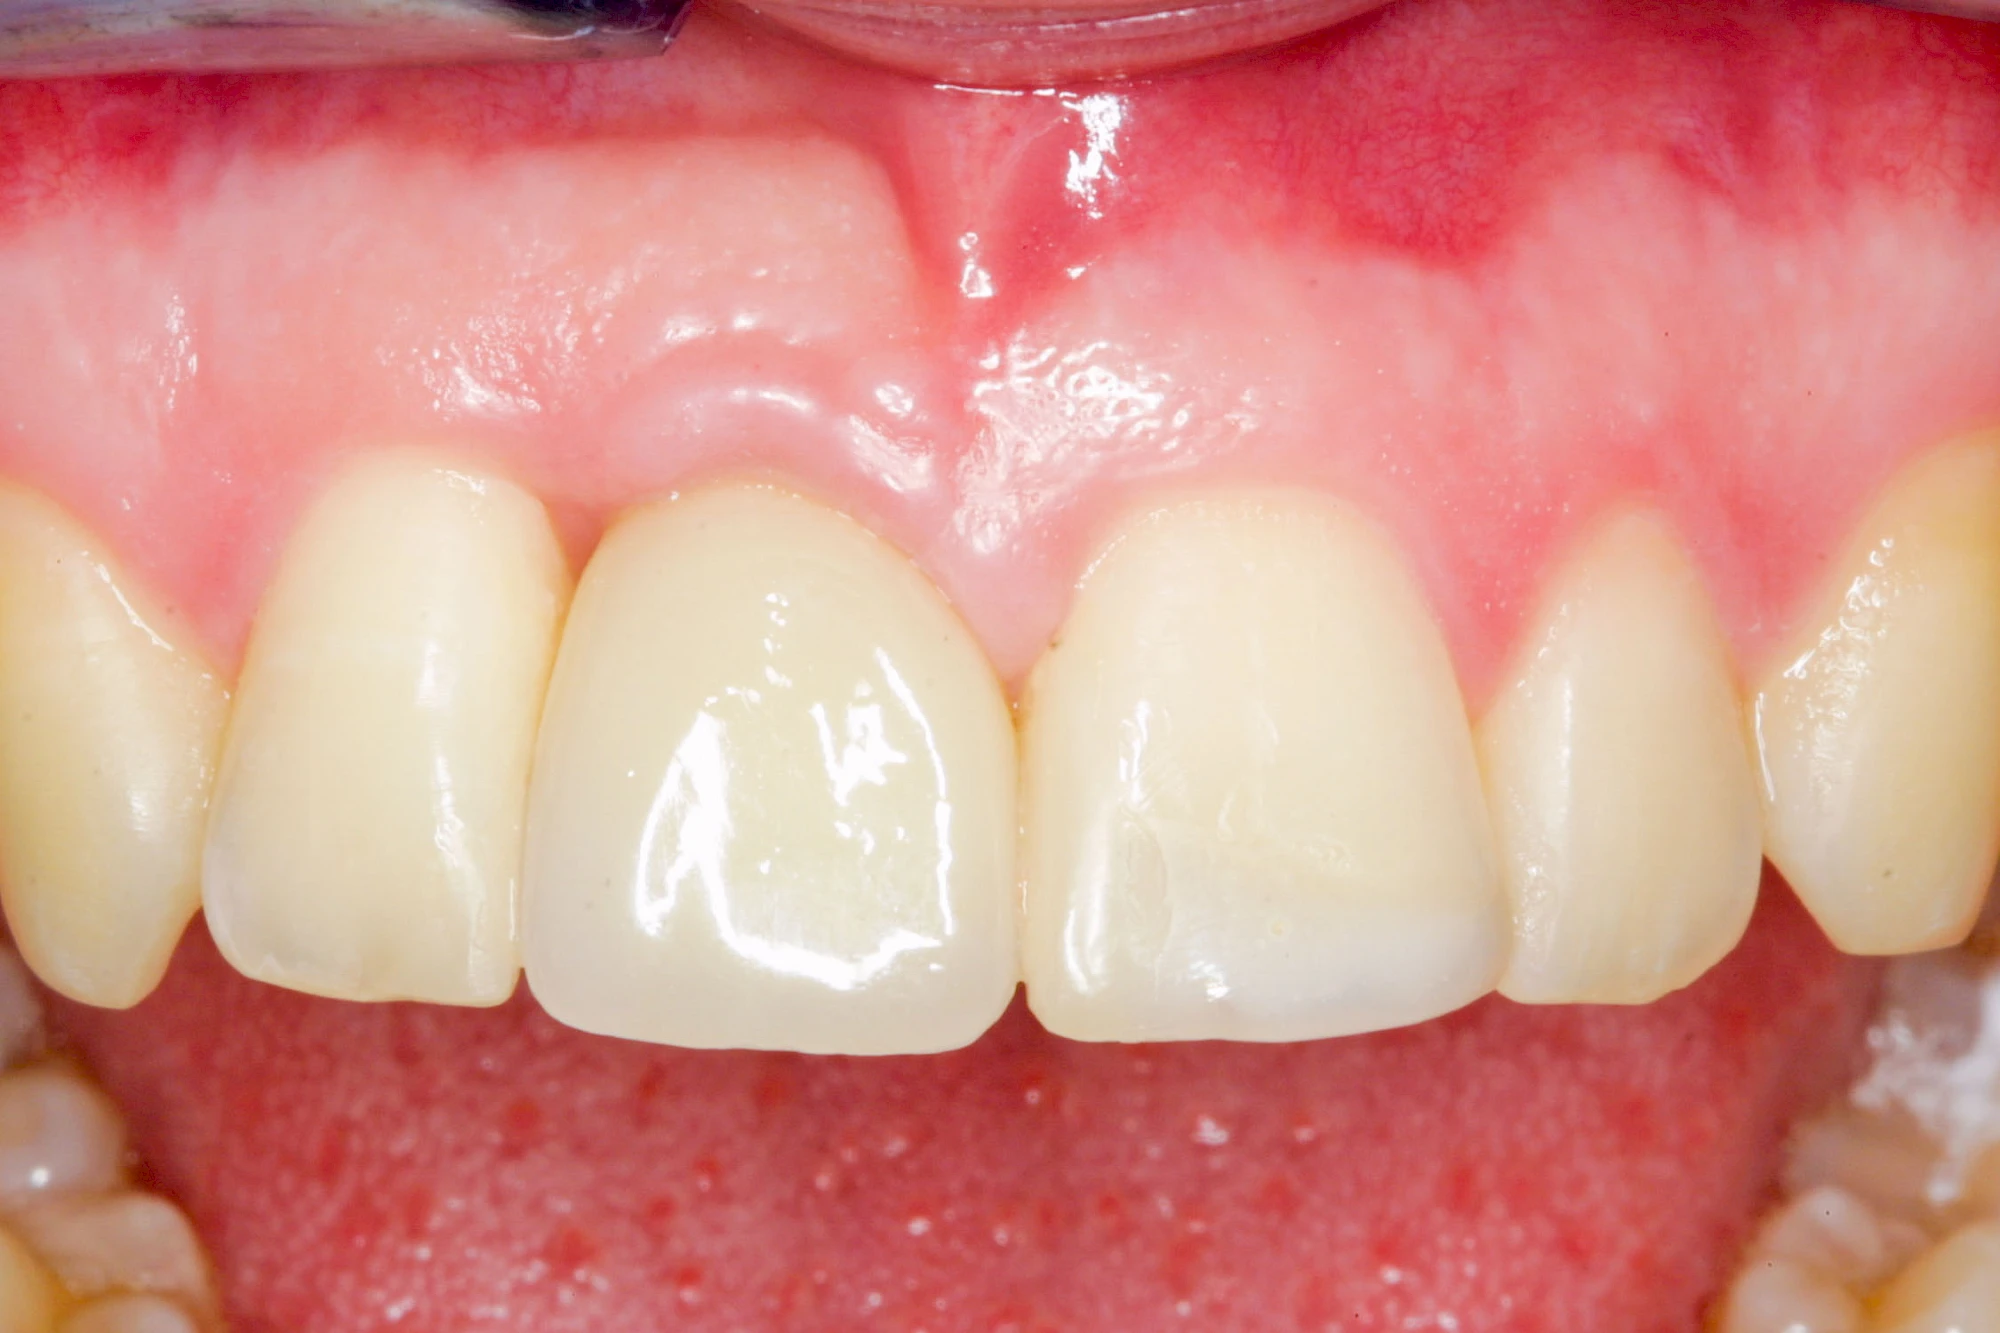

Fehlen einzelne Zähne und die Nachbarzähne sind unbeschadet oder gut zahnärztlich versorgt, werden immer häufiger Implantate gewählt, um die Lücken zu schließen. Auch bei größeren oder verteilten Lücken, wenn keine herausnehmbare Prothese gewünscht ist, werden Implantate für Kronen- bzw. Brückenversorgungen gesetzt. In Einzelfällen entscheiden sich sogar zahnlose Patienten für eine festsitzende Versorgung auf Implantaten.

Varianten zur Verankerung von festsitzendem Zahnersatz auf Implantaten